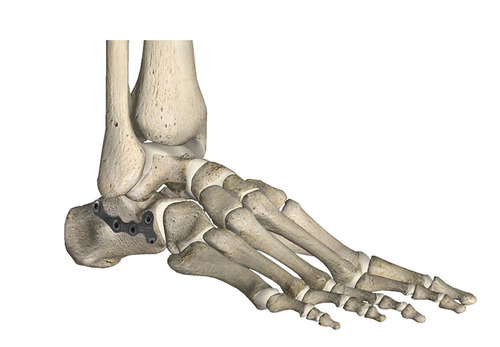

3.5/4.0跟骨锁定板

3.5/4.0跟骨锁定板 5孔 分左右

3.5/4.0跟骨锁定板 12孔 大、小 分左右

微创跟骨锁定板